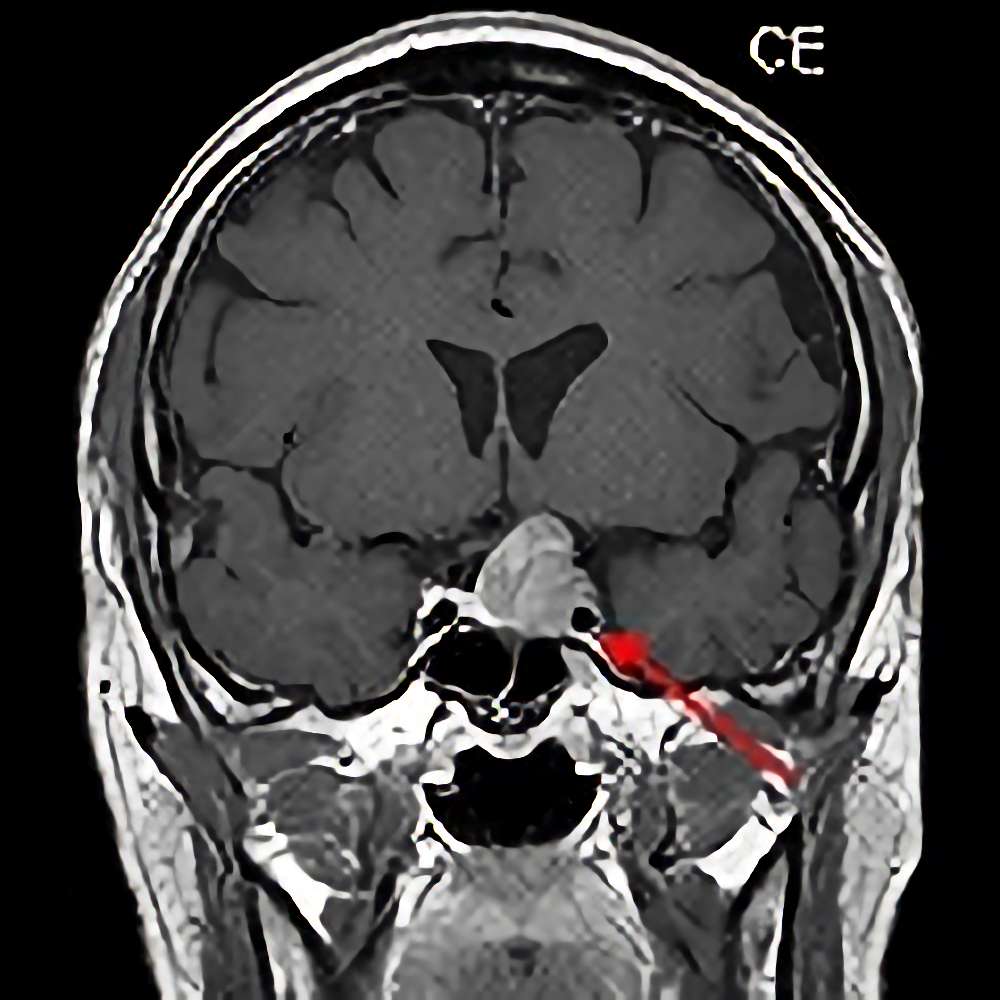

聴神経鞘腫

No.’14_1 手術前1

No.’14_1 摘出 前

No.’14_1 摘出 後